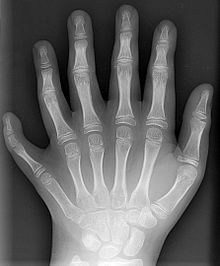

Mit Röntgenstrahlung kann der menschliche Körper durchleuchtet werden, wobei vor allem Knochen, aber bei modernen Geräten auch innere Organe sichtbar werden. Dabei wird ausgenutzt, dass das in den Knochen vorkommende Element Calcium mit Z=20 eine deutlich höhere Ordnungszahl hat als die Elemente, aus denen die weichen Gewebe hauptsächlich bestehen, nämlich Wasserstoff (Z=1), Kohlenstoff (Z=6), Stickstoff (Z=7) und Sauerstoff (Z=8). Neben herkömmlichen Geräten, die eine zweidimensionale Projektion produzieren, werden auch Computertomographen eingesetzt, die eine räumliche Rekonstruktion des Körperinneren ermöglichen. Man kann mit Röntgenstrahlen allerdings auch Krebs bekämpfen, indem man die Krebszellen, die i.A. strahlungsempfindlicher als das umgebende Gewebe sind, im Rahmen einer Strahlentherapie durch gezielte Bestrahlung schädigt.

Da die genannten Wissenschaftler ihre Kenntnisse nicht bekanntgaben, wusste auch Röntgen nichts davon. Er hat die Röntgenstrahlung unabhängig entdeckt, als er fluoreszenzfähige Gegenstände nahe der Röhre während des Betriebs der Kathodenstrahlröhre beobachtete, die trotz einer Abdeckung der Röhre (mit schwarzer Pappe) hell zu leuchten begannen. Röntgens Verdienst ist es, die Bedeutung der neu entdeckten Strahlen früh erkannt und diese als erster wissenschaftlich untersucht zu haben. Zu Röntgens Berühmtheit hat sicherlich auch die Röntgenaufnahme einer Hand seiner Frau beigetragen, die er in seiner ersten Veröffentlichung zur Röntgenstrahlung abbildete. Diese Berühmtheit trug ihm 1901 den ersten Nobelpreis für Physik ein, wobei das Nobelpreiskomitee die praktische Bedeutung der Entdeckung hervorhob. Röntgen nannte seine Entdeckung X-Strahlen.